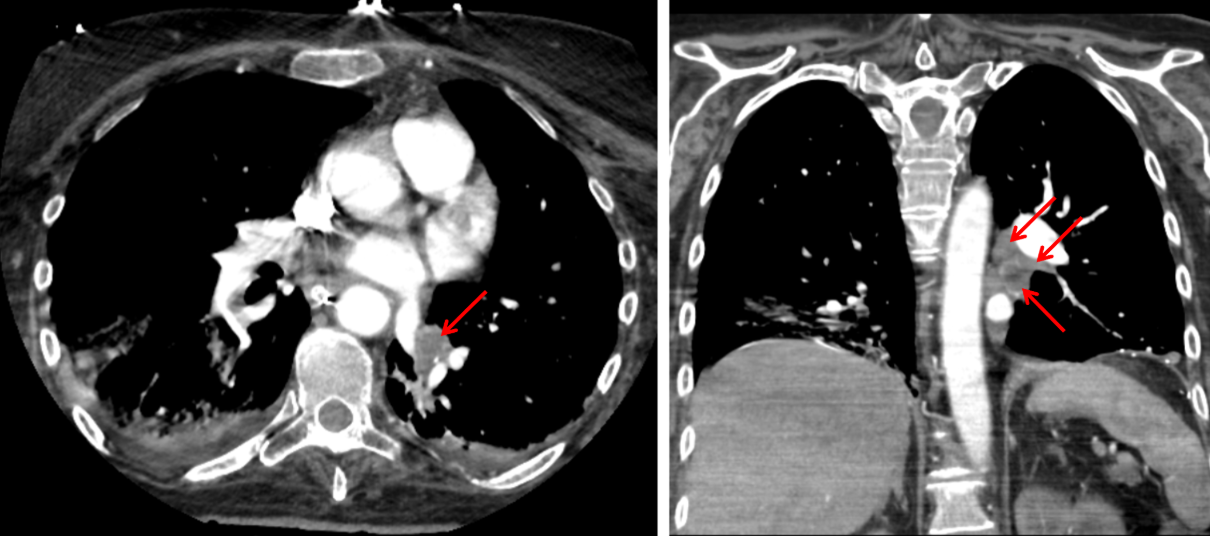

Annotated Images & Illustrations

Soft tissue attenuation material filling left lower lobe bronchi (red arrows), most concerning for large volume aspiration.